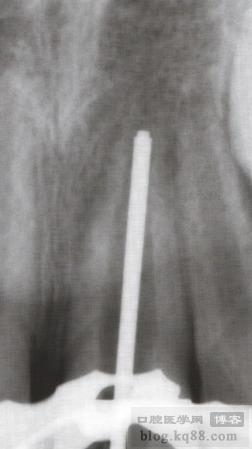

1、拍術(shù)前片確定牙根長度和根尖敞開直徑

3、根管干燥后試MTA輸送器,應(yīng)短于牙根1-2mm

4、玻璃板上調(diào)好MTA后將其置于輸送器內(nèi)送達(dá)根尖,紙尖倒置或小號垂直加壓器輕輕壓實

5、繼續(xù)輸送,直至MTA達(dá)到5mm以上然后壓實壓平,拍片確認(rèn)后,MTA上放一濕棉球以便于MTA更好的凝固,然后冠部開口雙層嚴(yán)密封閉